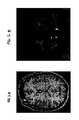

FIG. 2A shows an axial Magnetic Resonance Image (MRI) of the brain with stimulation lead electrodes in the anterior limb of the internal capsule embodiment;

FIG. 2B shows a coronal MRI of the brain with stimulation lead electrodes in the anterior limb of the internal capsule embodiment;

FIG. 2A shows an axial Magnetic Resonance Image (MRI) of the brain with stimulation lead electrodes in the anterior limb of the internal capsule embodiment.FIG. 2B shows a coronal MRI of the brain with stimulation lead electrodes in the anterior limb of the internal capsule embodiment. In one embodiment of the invention, the change in neuronal activity resulting from stimulation is measured by functional magnetic resonance imaging to confirm the efficacy of the stimulation. Further, the detected change in neuronal activity may also be used to feedback to thesignal generator10 to control the parameters of stimulation applied to the lead or even whether to apply stimulation at all.